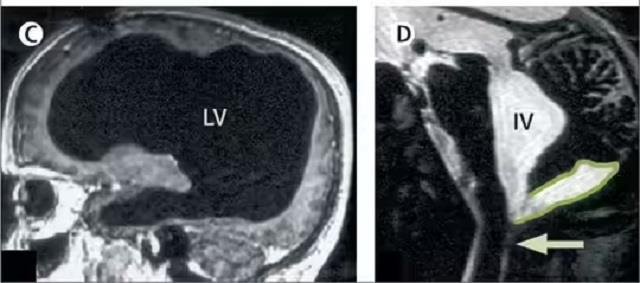

डेस्क: मेडिकल जगत में कई बार ऐसे चमत्कार होते हैं जो विज्ञान की सीमाओं को पार कर जाते हैं। ऐसा ही एक हैरान कर देने वाला मामला साल 2007 में सामने आया था, जब फ्रांस के 44 वर्षीय व्यक्ति के दिमाग का 90% हिस्सा खत्म हो चुका था, फिर भी वह सामान्य जीवन जी रहा था। डॉक्टरों ने जब उसका CT स्कैन देखा, तो वे भी दंग रह गए।

‘द लैंसेट’ में प्रकाशित इस केस रिपोर्ट के अनुसार, उस व्यक्ति के सिर में दिमाग की जगह तरल पदार्थ भरा हुआ था, और केवल एक पतली परत में ब्रेन टिश्यू बचा था। इसे हाइड्रोसेफेलस नामक स्थिति कहा जाता है, जिसमें दिमाग के अंदर तरल पदार्थ (cerebrospinal fluid) जमा हो जाता है।

रिपोर्ट के अनुसार, जब वह व्यक्ति सिर्फ 6 महीने का था, तब उसे पोस्टनैटल हाइड्रोसेफेलस हुआ था, जिसके इलाज के लिए उसके सिर में शंट सर्जरी की गई थी। 14 साल की उम्र में भी उसे पैर में कमजोरी और चलने में परेशानी महसूस हुई थी, लेकिन इलाज के बाद वह पूरी तरह ठीक हो गया। बाद में 44 साल की उम्र में दोबारा पैर में कमजोरी आने पर उसका CT और MRI स्कैन किया गया, और तब पता चला कि उसका लगभग पूरा दिमाग तरल पदार्थ से भरा हुआ है।